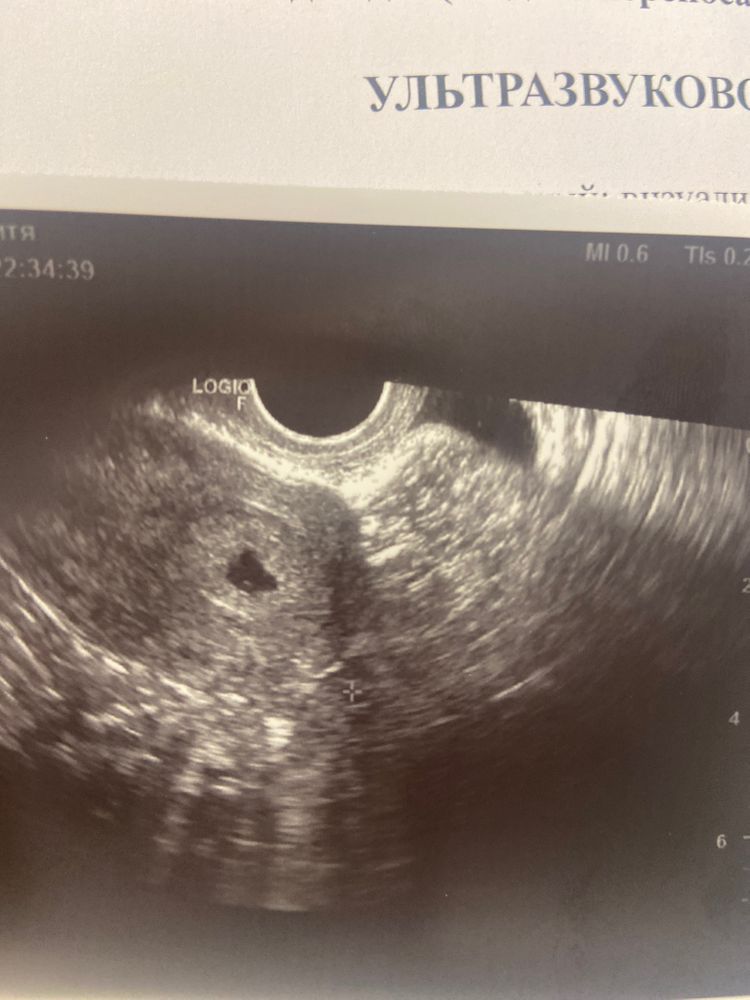

У меня ПЯ вроде как тоже не идеальной формы, но врач насчет этого ничего не сказала. Правда, мне УЗИ по животу делали, может из-за нажатия датчиком оно немного "приплюснулось".